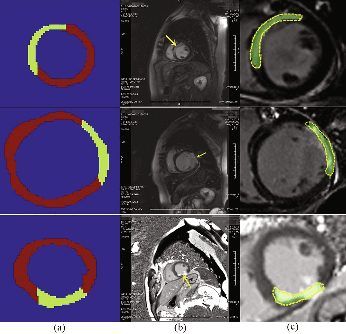

Abstract:Accurate detection of the myocardial infarction (MI) area is crucial for early diagnosis planning and follow-up management. In this study, we propose an end-to-end deep-learning algorithm framework (OF-RNN ) to accurately detect the MI area at the pixel level. Our OF-RNN consists of three different function layers: the heart localization layers, which can accurately and automatically crop the region-of-interest (ROI) sequences, including the left ventricle, using the whole cardiac magnetic resonance image sequences; the motion statistical layers, which are used to build a time-series architecture to capture two types of motion features (at the pixel-level) by integrating the local motion features generated by long short-term memory-recurrent neural networks and the global motion features generated by deep optical flows from the whole ROI sequence, which can effectively characterize myocardial physiologic function; and the fully connected discriminate layers, which use stacked auto-encoders to further learn these features, and they use a softmax classifier to build the correspondences from the motion features to the tissue identities (infarction or not) for each pixel. Through the seamless connection of each layer, our OF-RNN can obtain the area, position, and shape of the MI for each patient. Our proposed framework yielded an overall classification accuracy of 94.35% at the pixel level, from 114 clinical subjects. These results indicate the potential of our proposed method in aiding standardized MI assessments.